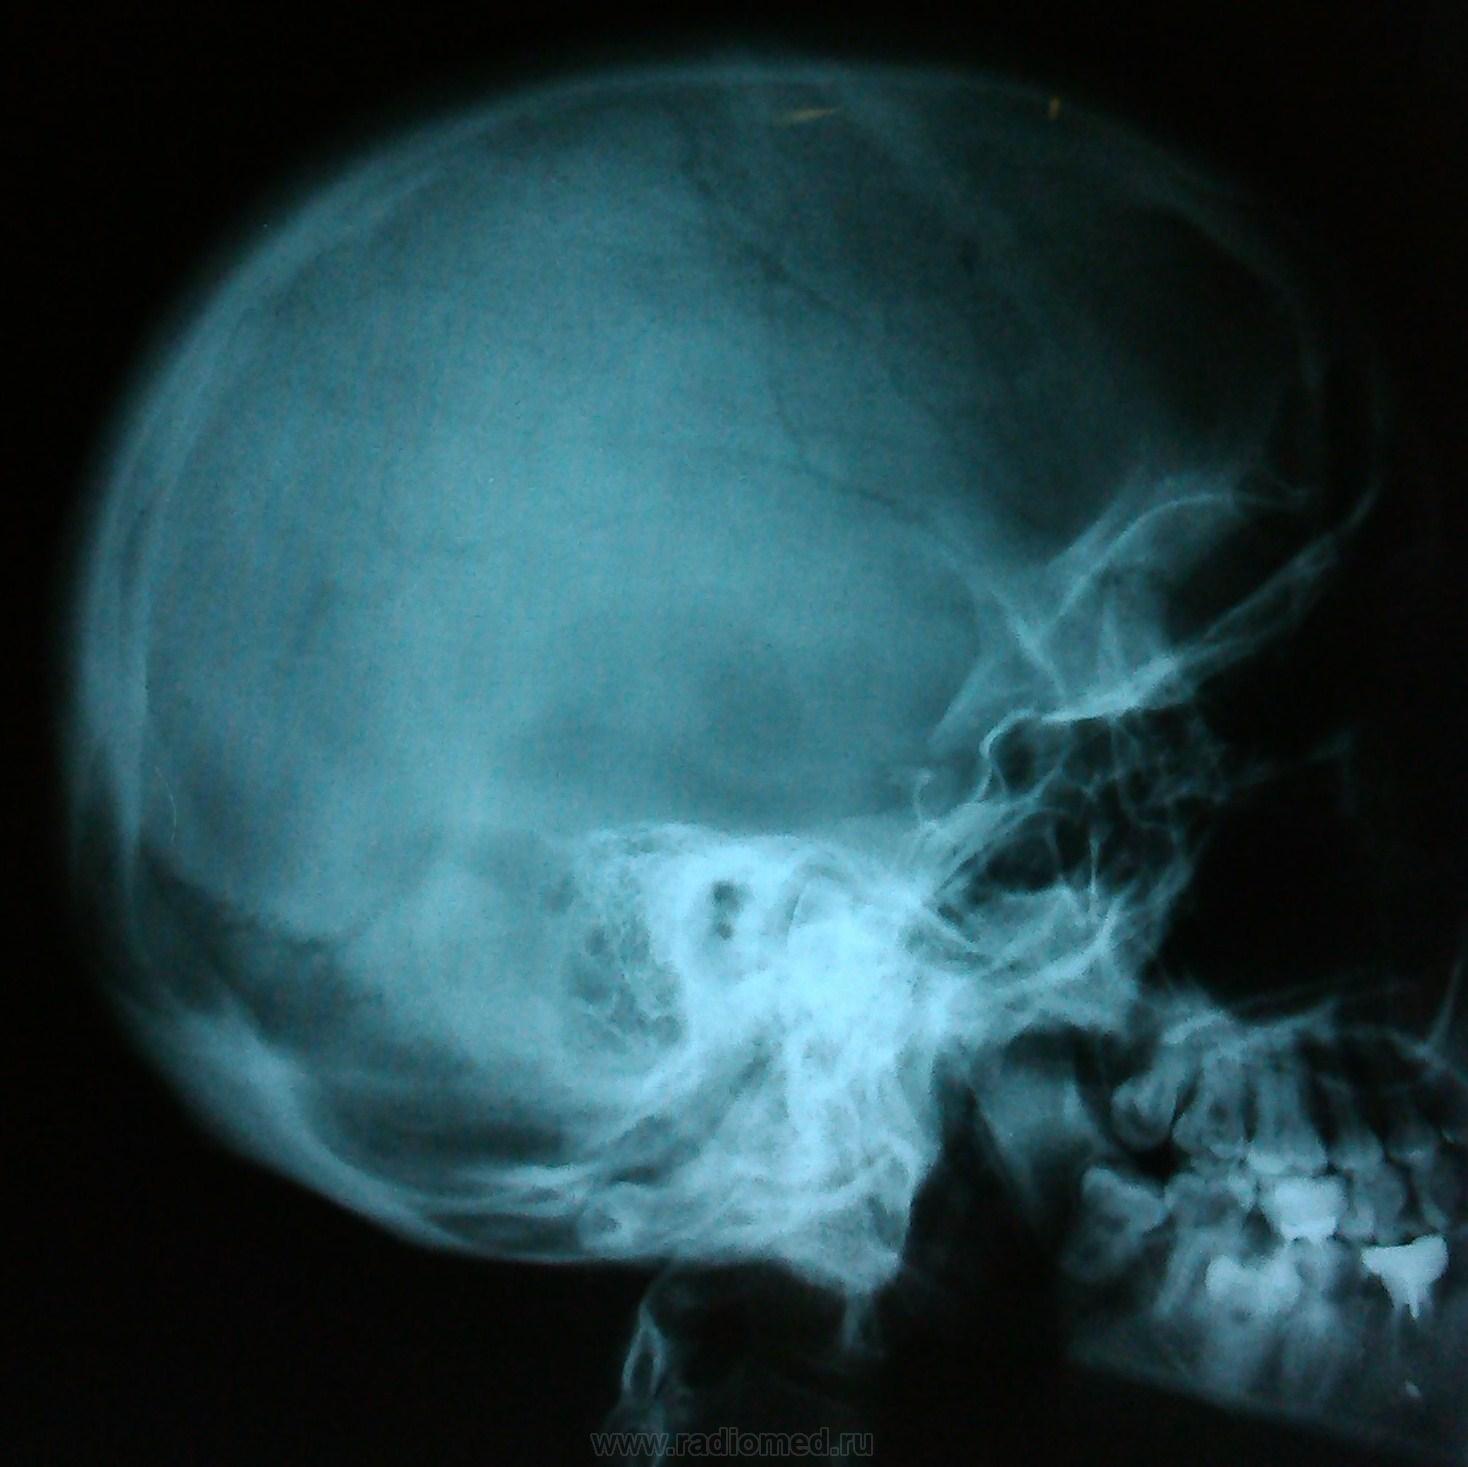

Пол пациента: Женский пол Тип патологии: Другое Область исследования: Челюстно-лицевая область и шея Методы исследования: Rg Пациентка, 31 г. В направление обследование. Со слов пациентки, упала, ударилась затылком. Есть ли какие-нибудь изменения?Подскажите, пожалуйста? https://radiomed.ru/sites/default/files/styles/case_slider_image/public/user/18609/img_20130917_112153.jpg?itok=mB5_QrQT ID:31806 Втр, 17/09/2013 - 15:57 #1 Kas10 Не на сайте Был на сайте: 12 лет 2 месяцев назад Зарегистрирован: 15.04.2012 - 14:53 Публикации: 5 Перелома не вижу. Втр, 17/09/2013 - 16:11 #2 Андрей Юрьевич Не на сайте Был на сайте: 1 день 12 часов назад Зарегистрирован: 16.11.2008 - 22:16 Публикации: 18098 Р-признаков костно-травматических повреждений не выявлено. Кстати, на затылочную кость есть дополнительная укладка. Андрей Юрьевич Втр, 17/09/2013 - 20:27 #3 Сергей Кузьминов Не на сайте Был на сайте: 1 год 1 неделя назад Зарегистрирован: 06.10.2012 - 15:51 Публикации: 11813 Не вижу перелома. Втр, 17/09/2013 - 20:35 #4 И.Бондаренко Не на сайте Был на сайте: 8 часов 23 минуты назад Зарегистрирован: 13.09.2011 - 22:55 Публикации: 9206 Признаков линии перелома не видно. Втр, 17/09/2013 - 22:23 #5 Алексей Игореви... Не на сайте Был на сайте: 6 лет 10 месяцев назад Зарегистрирован: 08.08.2012 - 21:52 Публикации: 786 Нету. "Обучая других - учишься сам". Н.И.Пирогов Ср, 18/09/2013 - 08:23 #6 ЧЮГ Не на сайте Был на сайте: 2 месяцев 2 недели назад Зарегистрирован: 31.10.2012 - 15:10 Публикации: 414 И.Бондаренко wrote: Признаков линии перелома не видно. +1

Перелома не вижу.

Р-признаков костно-травматических повреждений не выявлено. Кстати, на затылочную кость есть дополнительная укладка.

Не вижу перелома.

Признаков линии перелома не видно.